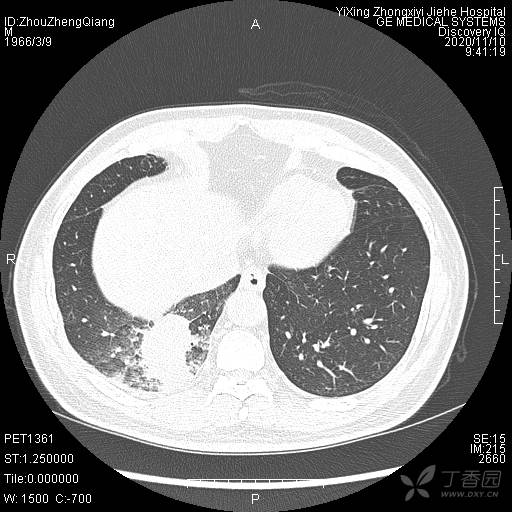

辅助检查:CT提示:右下肺占位伴周围炎症,CA待排,右侧少许胸腔积液。

临床诊断:右肺癌?待进一步检查。